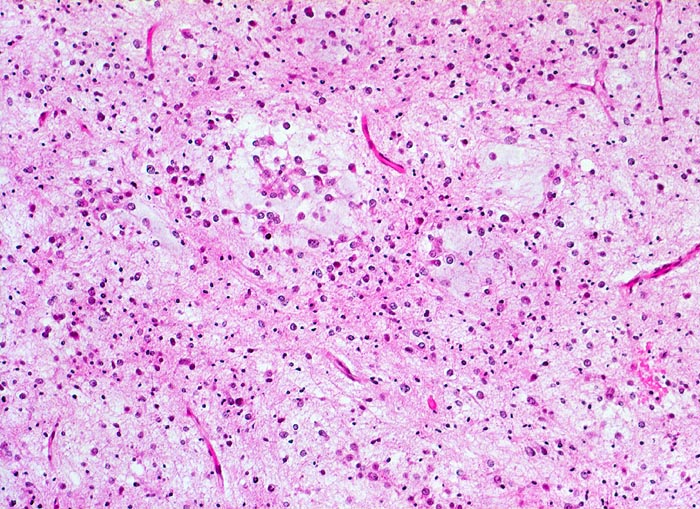

Histologisch bestehen die Oligodendrogliome aus kompakten Aggregaten runder Zellen mit deutlichen Zellgrenzen und klarem Zytoplasmasaum um einen dichten runden zentralen Kern (“Spiegelei”). Die Vakuolisierung des Zytoplasma stellt einen Fixationsartefakt dar und fällt bei Schnellschnitten als diagnostisches Hilfsmittel weg (Gefrierschnitt!). Charakteristisch sind verzweigte Kapillaren. Die Tumorzellen infiltrieren die Hirnrinde diffus und können sich bis in die Meningen ausbreiten.

• Tumorzellen umgeben von einem Halo ("Spiegeleier").

• Die Tumorzellen erinnern an Oligodendrozyten der weissen Substanz, haben aber deutlich grössere Kerne.

• Im Gegensatz zum Glioblastoma multiforme monomorphes Zellbild.